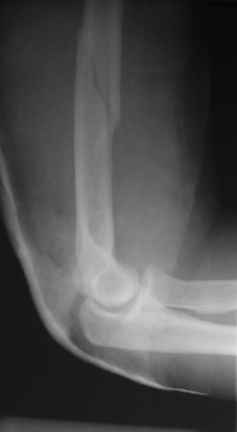

Теперь непосредственно по больному. Лечим функциональной повязкой, добились вот чего (приложение). Будем признательны за дальнейший комментарий - мое мнение, что можно продолжить без операции.

Имя     : Боковой.JPG

Имя     : Прямой.JPG